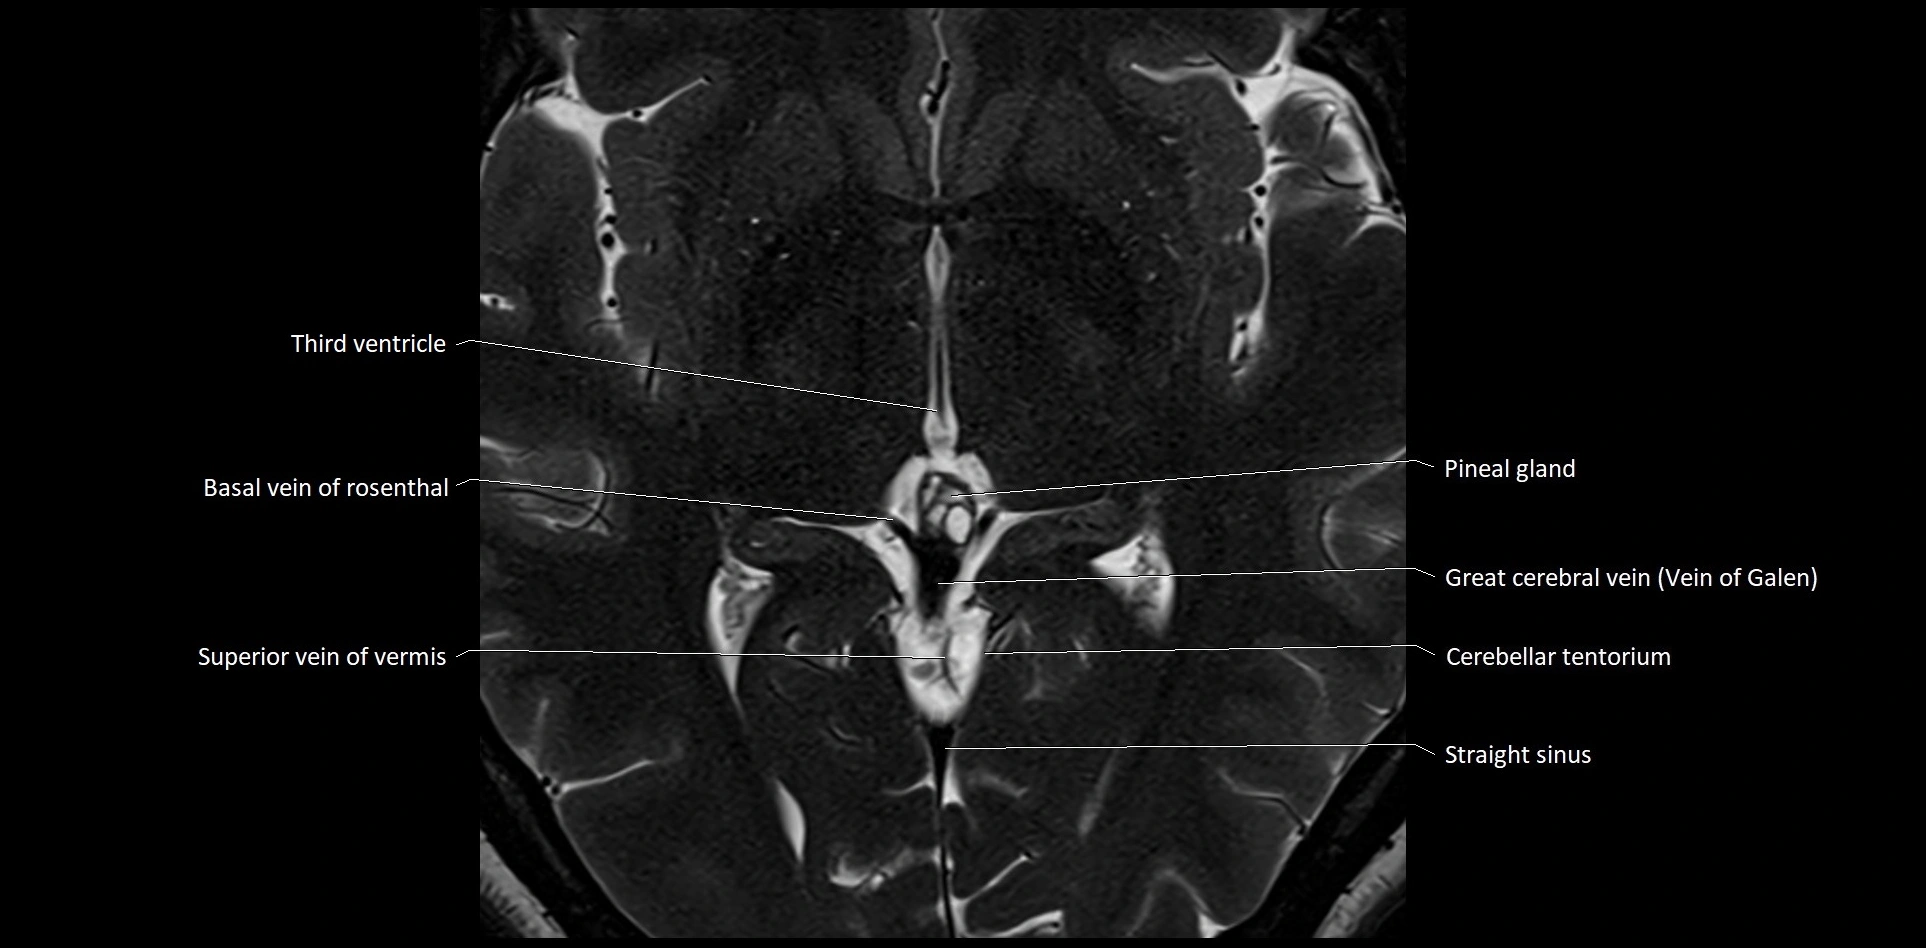

- Pineal gland

- Straight sinus

- Superior vein of vermis

- Superior vermian vein

- Transverse sinus